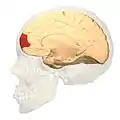

Brodmann area 10 (BA10, frontopolar prefrontal cortex, rostrolateral prefrontal cortex, or anterior prefrontal cortex) is the anterior-most portion of the prefrontal cortex in the human brain.[1] BA10 was originally defined broadly in terms of its cytoarchitectonic traits as they were observed in the brains of cadavers, but because modern functional imaging cannot precisely identify these boundaries, the terms anterior prefrontal cortex, rostral prefrontal cortex and frontopolar prefrontal cortex are used to refer to the area in the most anterior part of the frontal cortex that approximately covers BA10—simply to emphasize the fact that BA10 does not include all parts of the prefrontal cortex.

BA10 is a subdivision of the cytoarchitecturally defined frontal region of cerebral cortex. It occupies the most rostral portions of the superior frontal gyrus and the middle frontal gyrus. In humans, on the medial aspect of the hemisphere it is bounded ventrally by the superior rostral sulcus. It does not extend as far as the cingulate sulcus. Cytoarchitecturally it is bounded dorsally by the granular frontal area 9, caudally by the middle frontal area 46, and ventrally by the orbital area 47 and by the rostral area 12 or, in an early version of Brodmann's cortical map (Brodmann-1909), the prefrontal Brodmann area 11-1909.[4]

Images

Animation.

Animation. front view.

front view. Lateral view.

Lateral view. Medial view.

Medial view.